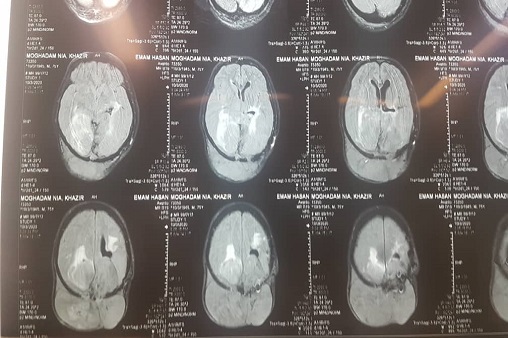

2 عمل جراحی خارج کردن تومور مغزی مننژیوم و عمل تومور هیپوفیز در بیمارستان صنایع پتروشیمی ماهشهر با موفقیت انجام شد.

به گزارش روابط عمومی بهداشت و درمان صنعت نفت ماهشهر، در 20 آبانماه یک عمل جراحی موفقیت آمیز تومور هیپوفیز در قائده جمجمه به روش آندوسکوپیک از راه بینی تخلیه شد.بیمار آقایی 57 ساله به علت کاهش بینایی و سردرد مراجعه کرده بود که در MRI  تشخیص آدنوم هیپوفیز داده شد عمل جراحی توسط دکتر امیر آذرهمایون با بیهوشی دکتر باستانی فر و تیم مجرب اتاق عمل بیمارستان نفت ماهشهر انجام شد و خوشبختانه تومور به طور کامل تخلیه شده و بیمار بعد از عمل بینایی کامل خود را بدست آورد و با حال عمومی خوب از بیمارستان ترخیص گردید.

بیمار مردی 60 ساله و از اهالی روستاها ی شهرستان بندرماهشهر بود که تومور بزرگی از نوع مننژیوم ، قسمت وسیعی از جمجمه وی را درگیر کرده بود .رشد این تومور به سمت داخل جمجمه بود که به بافت مغزی نفوذ کرده و طی چند سال با رشد بیش از اندازه باعث شده بود بیمار دچار contexity  (تحدب مغزی) و برجستگی غیر طبیعی در سر و همچنین کاهش دید شود.این عمل توسط تیم جراحی متشکل از دکتر آذرهمایون جراح مغز واعصاب، دکتر چهارمحالی متخصص بیهوشی ، پرستاران و کادر مجرب اتاق عمل در مدت 3 ساعت انجام شد که پس از پایان عمل بیمار به بخش مراقبتهای ویژه منتقل شد و پس از سه روز با حال عمومی خوب از بیمارستان مرخص گردید.